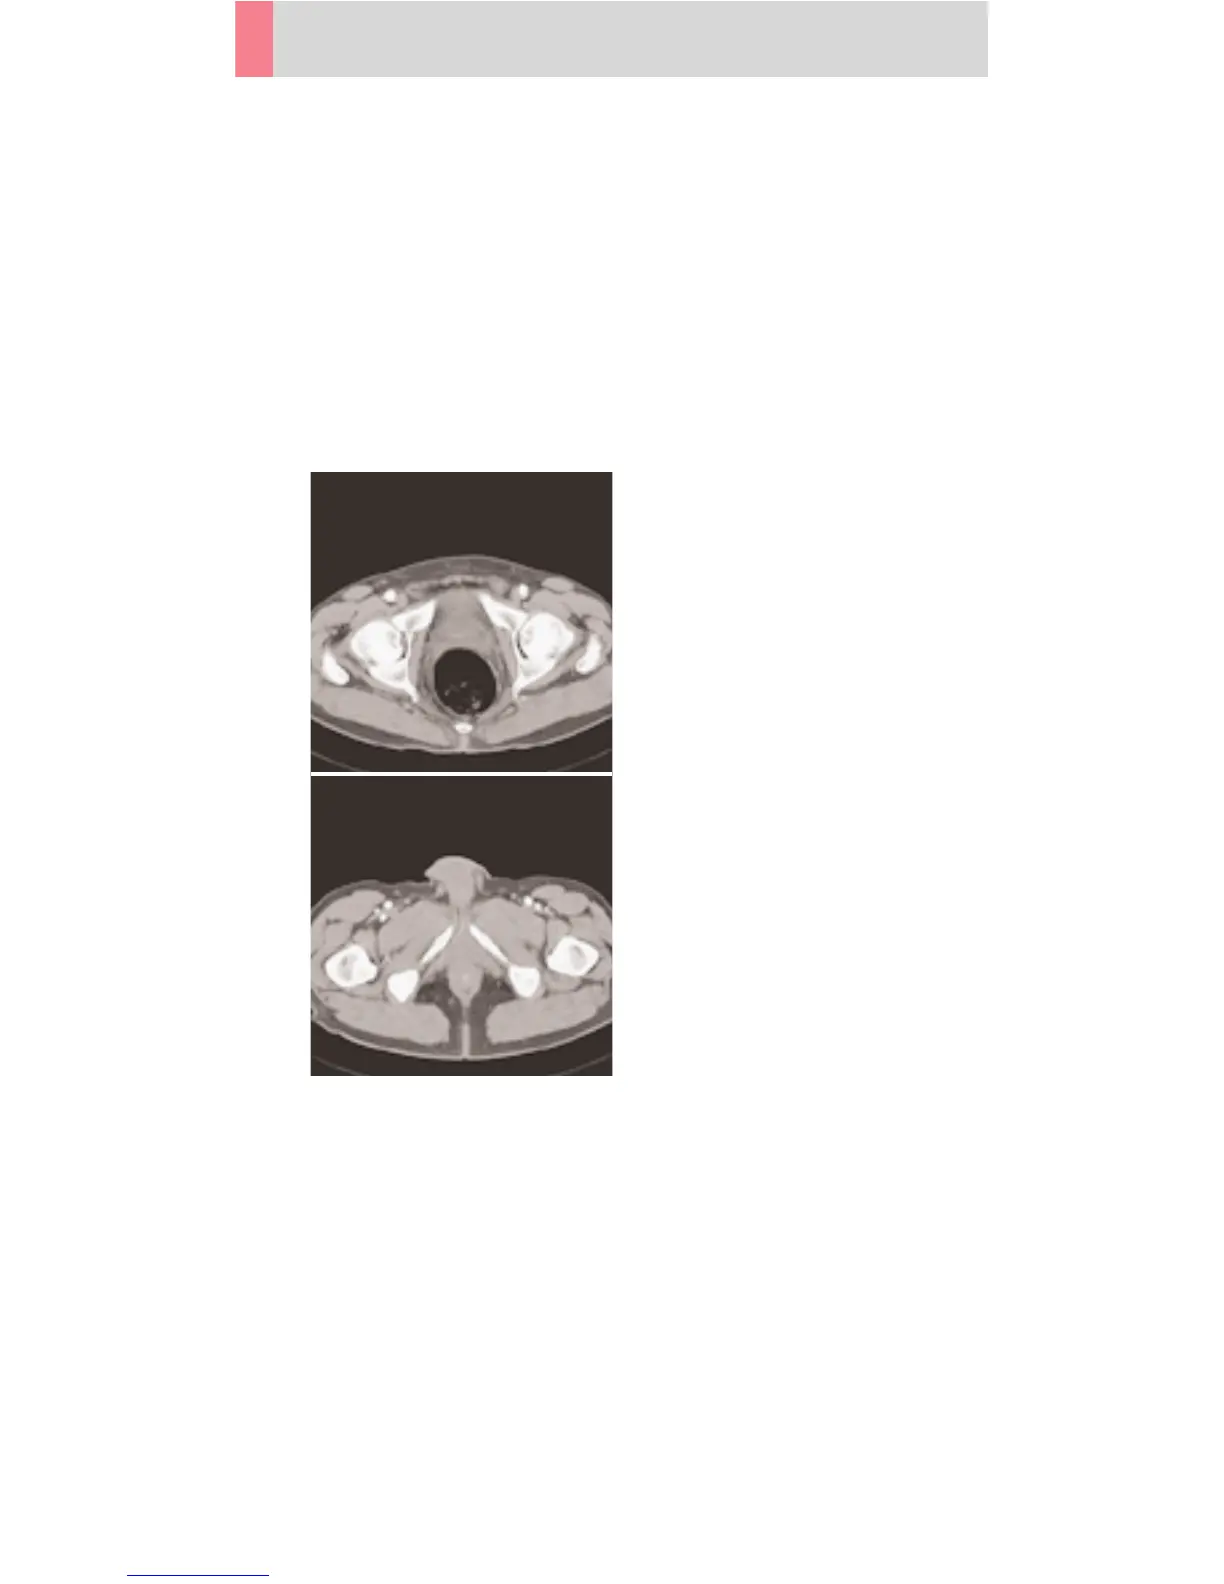

Pelvis

PelvisRoutine

Spiral mode for routine pelvis studies. E. g. processes

of the prostate, urinary bladder, rectum, gynecological

indications etc.

A typical range of 20 cm will be covered in 13.1 sec.